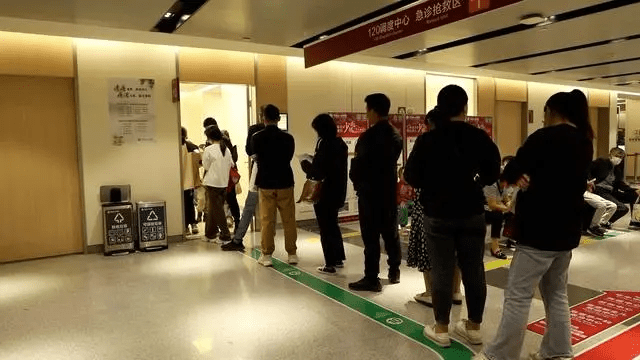

综合媒体报道,近日全国多地都出现呼吸道疾病患者挤满医院的情况,医院的轮候人数多达数百人,当中以儿科最为严重。

▲病童家长在门口排队形成长龙。新华社